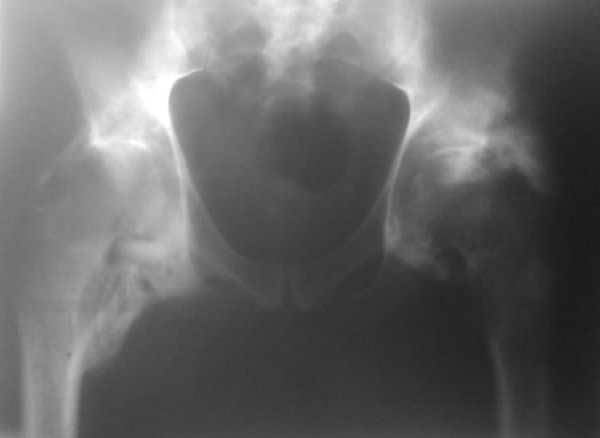

уважаемые коллеги, на консультацию обратился пациент 38 лет нейрогенной гетеротопической оссификацией. Около полугода назад был геморрагический инсульт, 1,5 мес в реанимации, был тетрапарез. в настоящее время имеется внутримозговая гемотома (нейрохирурги решили "не трогать"), неврологически - с положительной динамикой, регресс до нижнего прарапареза, АД стабилизировано, соматически тоже с положит динамикой. Движения в коленных и голеностопных суставах в удовлетворительном объеме. ограничение движений в локтевых, плечевых суставах. Помогите определиться с тактикой в отношении тазобедренных суставов (движений нет, фиксированное положение в сгибании 170, 0 ротации). качество снимка - не очень, представляется, что сами суставные поврехности изменены незначительно. буду благодарен за литературу по этому вопросу в электронном виде, если у кого есть. Характер вмешательств (артролиз/THR), сроки, доступы? послеоперационная профилактика?С уважением, Maxim Agalakov

сожалею о качестве снимков (телефон) но когда смотрел их "вживую", впечатление, что суставные щели далеко не сомкнулись

Надо новый телефон купить с более высоким разрешением камеры, или сделать новые снимки, прямой таз (на снимке почти инлет), в абдукции и аддукции конечности для определения амплитуды движения вообще.

В гетеротопические оссификации вокруг тазобедренного сустава иногда вовлекается седалищный нерв.

"Napkin Ring Sign" называется когда седалищный нерв замурован в оссификат.

КТ поможет разобраться имеется ли вовлечение нерва.

После удаления оссификации улучшится состояние сустава, откроется суставная щель.

ЕСЛИ Я НЕ ОШИБАЮСЬ ТО НА СНИМКЕ ВИДНЫ ПРИМЕТЫ ФОРМИРОВАНИЯ КОСТНОГО АНКИЛОЗА. ЧТО СЧИТАЮТ КОЛЕГИ.